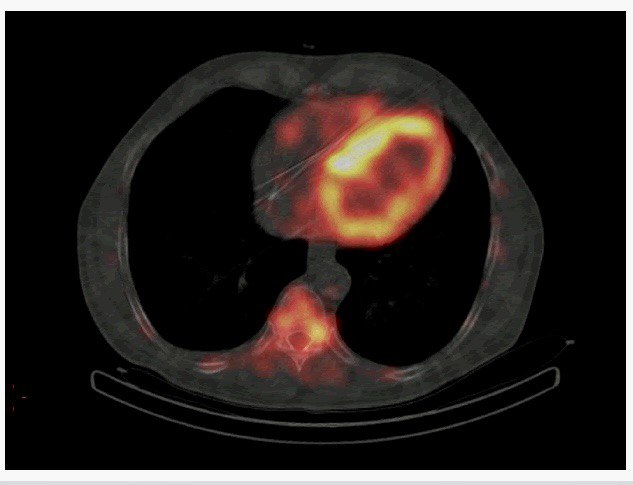

В госпитале имени А. А. Вишневского внедрили в широкую практику новый вид диагностики амилоидоза сердца — сцинтиграфию. Это высокочувствительный неинвазивный метод диагностики заболевания, который ранее делали только военнослужащим.

Как сообщили в кардиологическом центре учреждения, ЦВКГ стал одним из десяти в списке столичных медицинских Центров, где возможно провести сцинтиграфию миокарда для подтверждения диагноза так называемого транстиретинового (АТТR) амилоидоза.

Данное исследование очень актуально для больных с клинической картиной сердечной недостаточности с сохранённой фракцией выброса (СНсФВ), нарушениями ритма и проводимости сердца, стенозом клапана аорты, которые пока даже не подозревают о наличии у них серьёзного заболевания. Своевременная диагностика ATTR-амилоидоза сердца и его эффективное лечение являются сложной проблемой в кардиологической практике. Это связано с относительно редкой распространённостью патологии, неспецифической клинической картиной заболевания, отсутствием в России специализированных центров, занимающихся проблемами амилоидоза.

Основными преимуществами сцинтиграфии миокарда являются: отсутствие применения йод-содержащего контрастного вещества (следовательно, риск аллергических реакций минимален); возможность проведения в амбулаторных условиях; высокая информативность и диагностическая точность исследования.